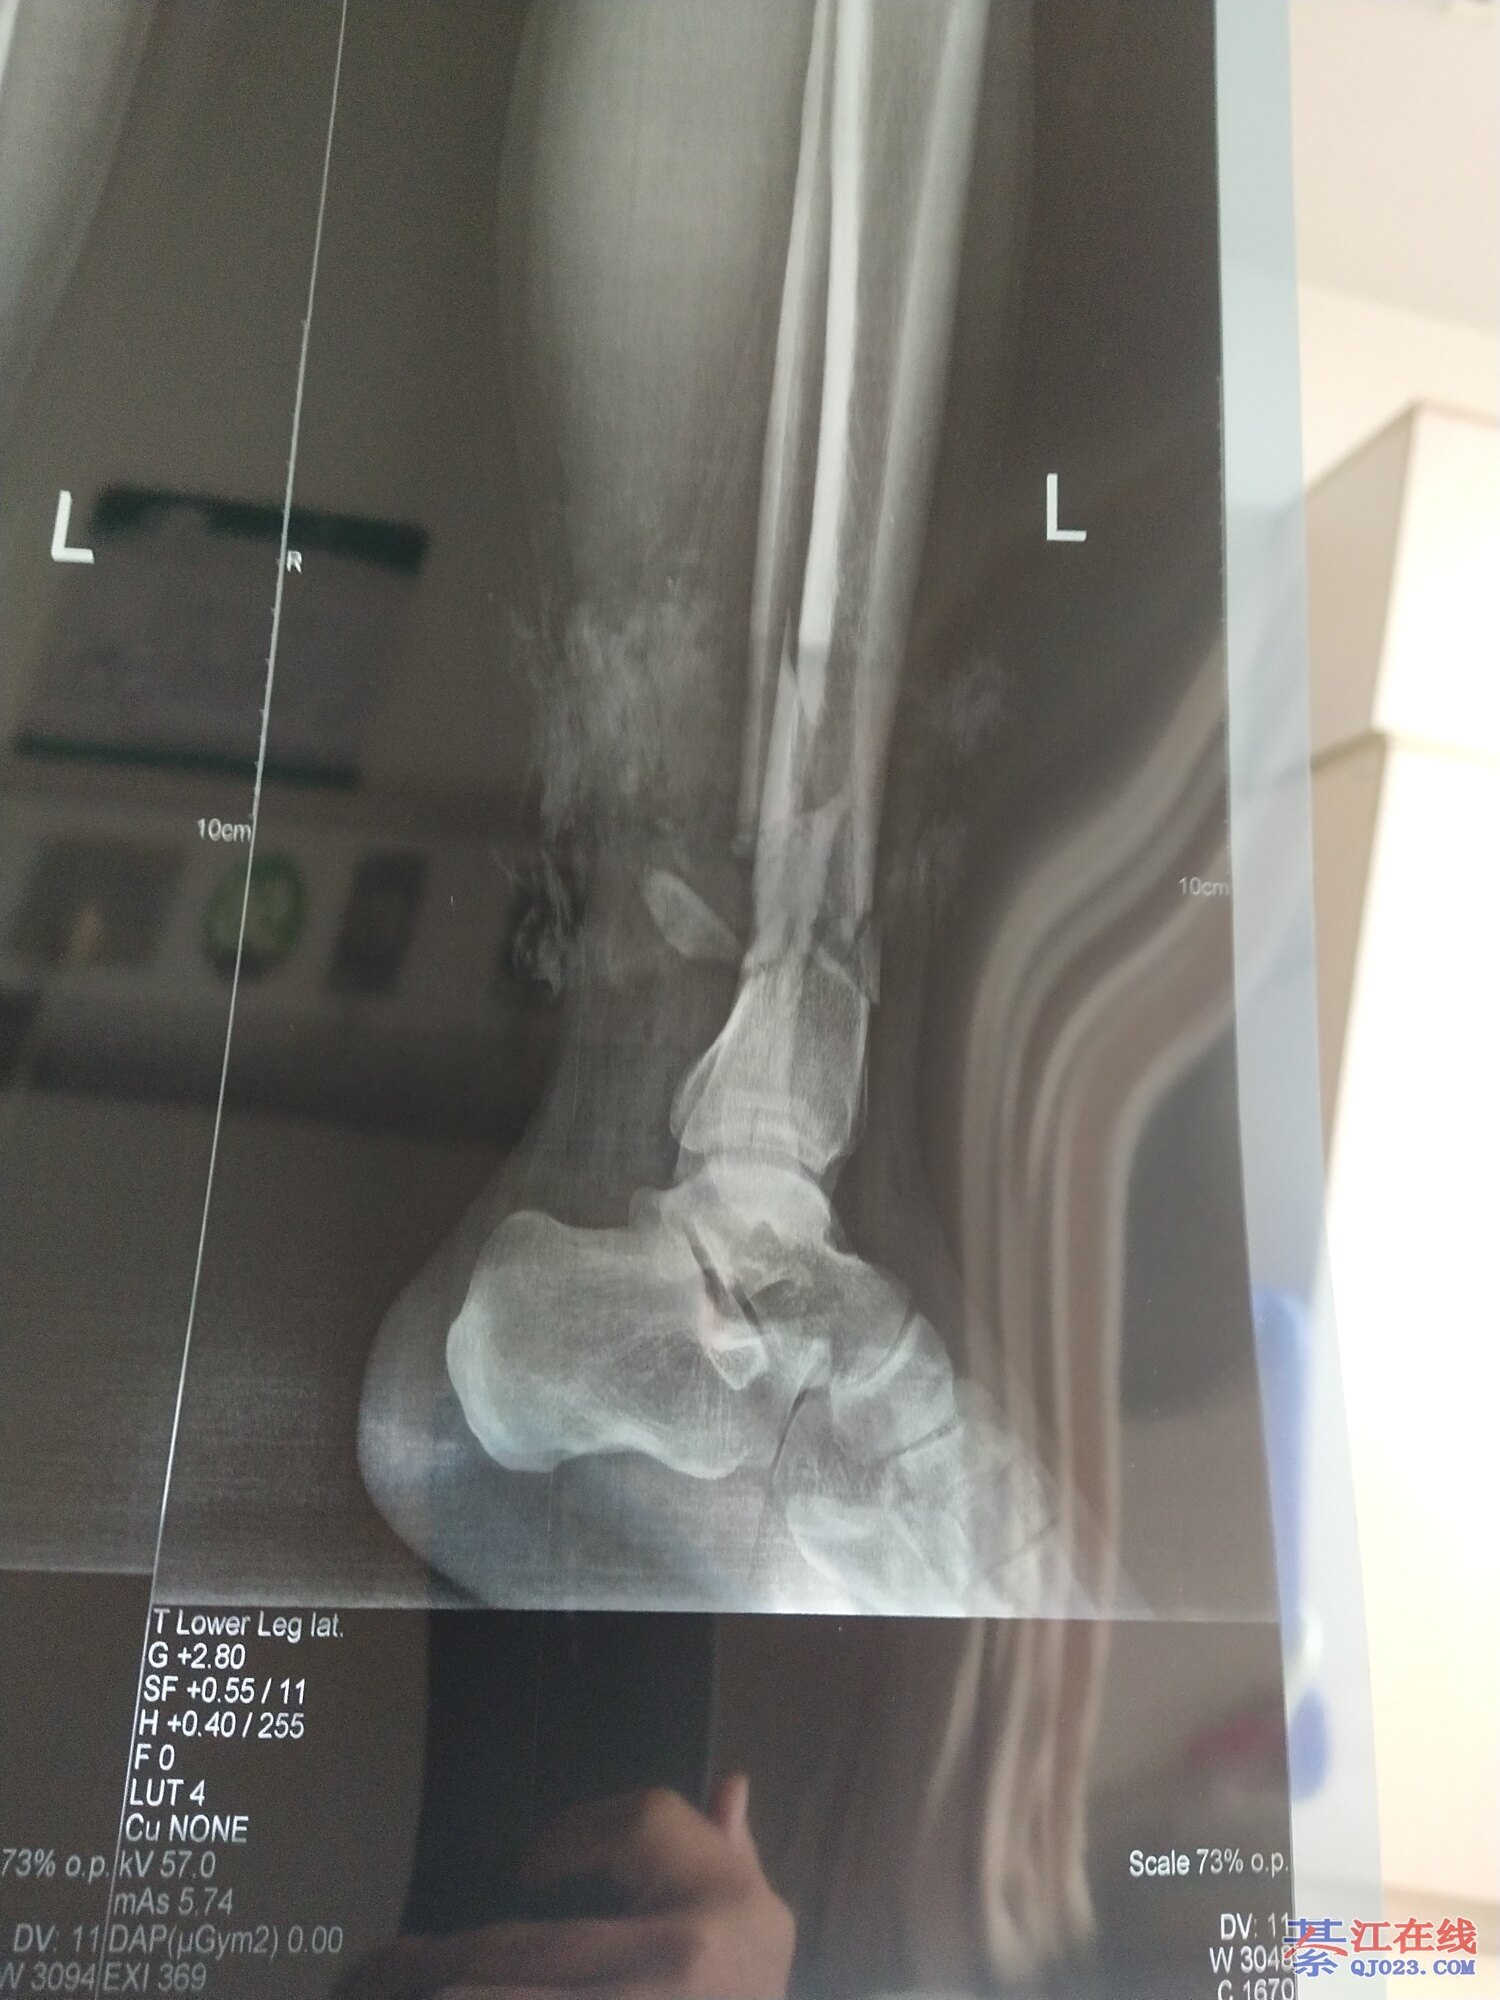

看到都疼,祝早日康复